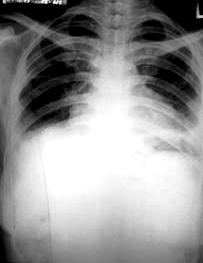

ภาพที่ 2. ภาพฉายรังสีทรวงอก เมื่อวันที่ 23 มกราคม พ.ศ. 2549

ที่โรงพยาบาลสระบุรี ภายหลังการใส่ท่อช่วยหายใจ 1 วัน

พบว่ามี interstitial infiltration และน้ำในช่องเยื่อหุ้มปอดมากกว่าเดิม.